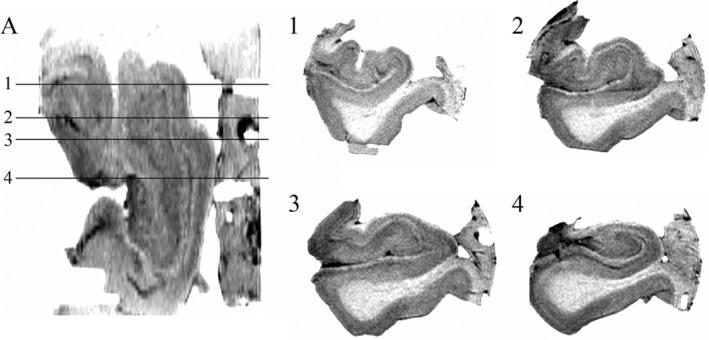

There is a growing body of literature studying changes in hippocampal subfields in a variety of different neurological conditions, but this work has mainly focused on the hippocampal body given challenges in visualization of hippocampal anatomy in the head and tail when sectioned in the typical coronal image plane. Curved multiplanar reformatting (CMPR) is an image reconstruction method that can improve visualization of complex three-dimensional structures. The objective of this study was to determine whether CMPR could facilitate visualization of the human hippocampal anatomy along the entire caudal-rostral axis. CMPR was applied to high-resolution magnetic resonance imaging acquired ex vivo on four cadaveric hippocampal specimens at 4.7 T (T2-weighted, 0.2 × 0.2 × 0.5 mm ). CMPR provided clear visualization of the classic "interlocking C" appearance of the dentate gyrus and cornu ammonis along the entire caudal-rostral axis including the head and tail, which otherwise show complex anatomy on the standard coronal slices. CMPR facilitated visualization of hippocampal anatomy providing the impetus to develop simplified approaches to delineate subfields along the entire hippocampus including the usually neglected head and tail.

越来越多的文献研究了各种不同神经状况下海马亚区的变化,但这项工作主要集中在海马体上,因为在典型的冠状影像平面上进行切片时,头部和尾部的海马解剖结构难以可视化。曲面多平面重建成像(CMPR)是一种可以改善复杂三维结构可视化的图像重建方法。本研究的目的是确定 CMPR 是否可以促进沿着整个头尾轴可视化人类海马解剖结构。CMPR 应用于在 4.7T 下离体采集的四个尸体海马标本的高分辨率磁共振成像(T2 加权,0.2×0.2×0.5mm)。CMPR 清晰地显示了齿状回和角回的经典“互锁 C”外观,沿着整个头尾轴,包括头部和尾部,而在标准冠状切片上,这些部位显示出复杂的解剖结构。CMPR 促进了海马解剖结构的可视化,为开发简化的方法来描绘整个海马体(包括通常被忽视的头部和尾部)的亚区提供了动力。